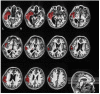

Disorders of consciousness are a heterogeneous mixture of different diseases or injuries. Although some indicators and models have been proposed for prognostication, any single method when used alone carries a high risk of false prediction. This study aimed to develop a multidomain prognostic model that combines resting state functional MRI with three clinical characteristics to predict one year-outcomes at the single-subject level. The model discriminated between patients who would later recover consciousness and those who would not with an accuracy of around 88% on three datasets from two medical centers. It was also able to identify the prognostic importance of different predictors, including brain functions and clinical characteristics. To our knowledge, this is the first reported implementation of a multidomain prognostic model that is based on resting state functional MRI and clinical characteristics in chronic disorders of consciousness, which we suggest is accurate, robust, and interpretable.